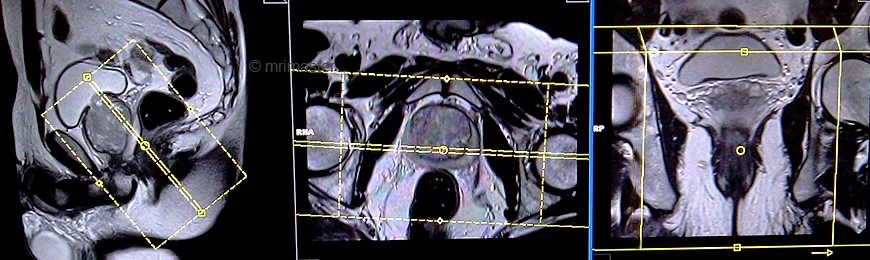

T2 tse sagittal 3mm SFOV pre proctogram

Plan the sagittal slices on the axial plane; angle the positioning block parallel to the interpubic fibrocartilage and the anal canal. Check the positioning block in the other two planes. An appropriate angle must be given in the coronal plane (parallel to the rectum and the anal canal). Slices must be sufficient to cover the whole pelvis from the right acetabulum to the left acetabulum. FOV must be big enough to cover the whole pelvis (normally 270mm-300mm). Adding saturation bands on top and front of the sagittal block will reduce artifacts from arterial pulsation and breathing.

TR 4000-5000 | TE 100-120 | SLICE 3 MM | FLIP 130-150 | PHASE A>P | MATRIX 320X320 | FOV 270-300 | GAP 10% | NEX(AVRAGE) 3 |

T2 TRUFISP cine, small FOV 10mm, 1 second, 150 measurements.

Plan the sagittal slices on the axial plane; angle the positioning block parallel to the interpubic fibrocartilage and the anal canal. Check the positioning block in the other two planes. An appropriate angle must be given in the coronal plane (parallel to the rectum and the anal canal). Slice must be positioned over the middle of the rectum and anal canal.

Parameters

TR 40-50 | TE 1-2 | SLICE 5-10 MM | FLIP 70 | PHASE A>P | MATRIX 208X208 | FOV 250-300 | OVERS. 50% | CINE 150measurement |